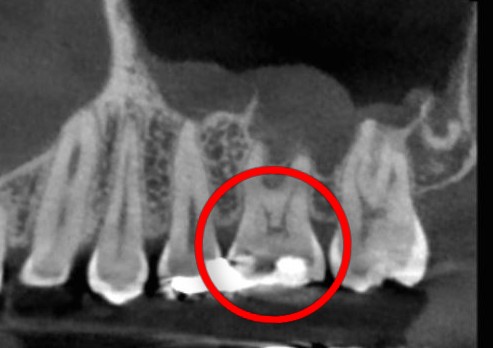

CTを撮った所、仮詰めの下が虫歯になっていました💦何もしなくても痛いということで、早急に仮詰めを外して中を確認しました!

仮詰めを外したところ、予想通り神経の入り口が出ていました💦